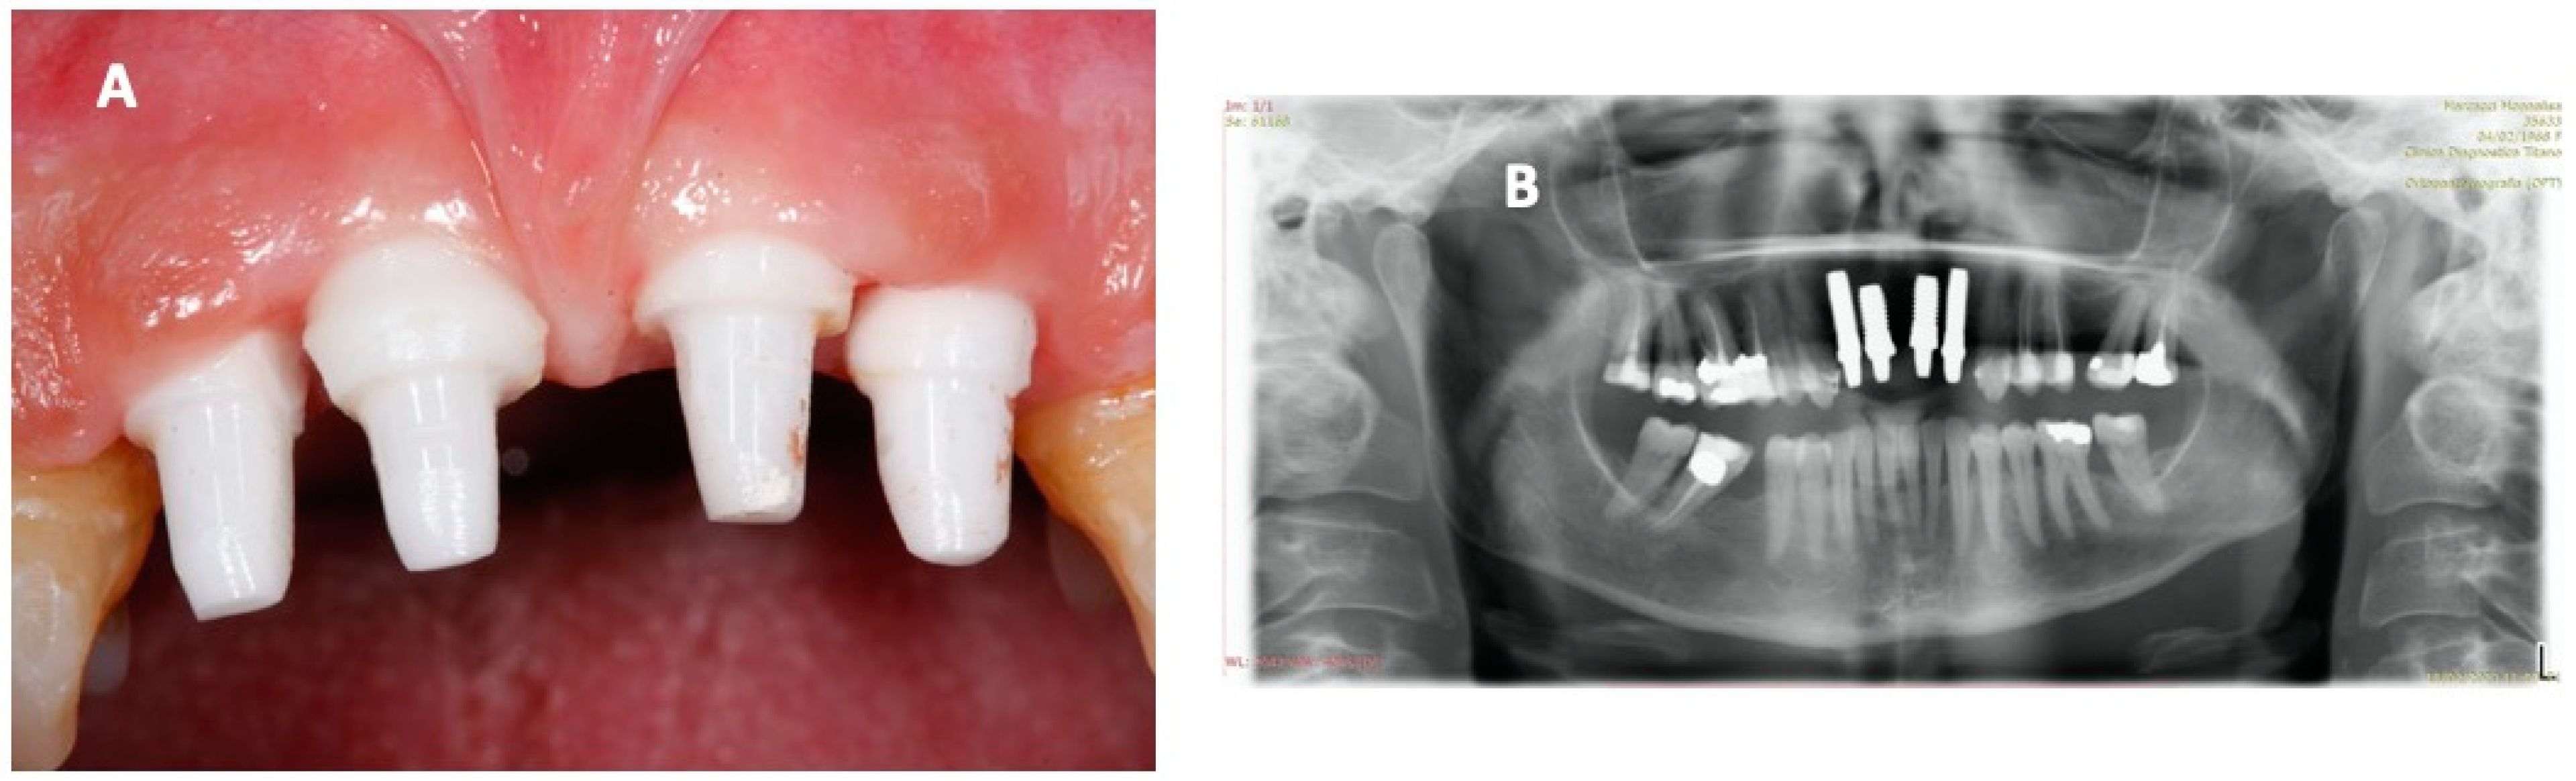

2. Case Report